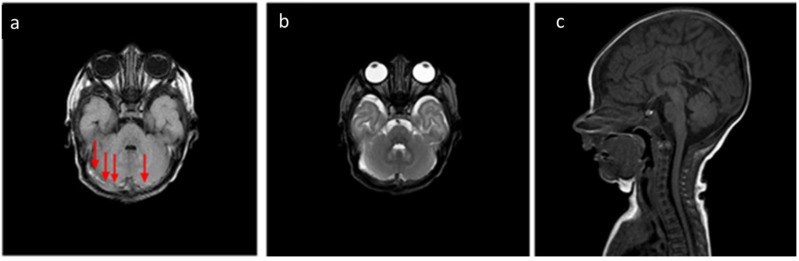

Background: Neonatal birth-related intracranial subdural hemorrhages (SDHs) represent a form of bleeding inside the skull that occurs in newborns. This condition includes the extravasation of blood both in the encephalic parenchyma and in the extra-axial spaces. Recent studies have shown that SDH and particularly post-traumatic birth-related hemorrhages represent a frequent occurrence, but they are often asymptomatic. The gold standard for the diagnosis and follow-up of patients with SDH is multiparametric Magnetic Resonance Imaging. The aim of this study is to describe our experience by reporting several cases of SDH with different distribution and Central Nervous System involvement by the MRI of this pathology in infants up to 30 days of age. Methods: We analyzed the age and sex of the patients included in this study, the localization of SDH in different CNS areas, and their frequency using distribution plots and pie charts. Results: About the analysis of the SDH locations in the 32 patients, the most common location was the cerebellum (31/32, 96.9%), followed by parietal and occipital lobes (19/32, 59.4%; 18/32, 56.2%, respectively), falx cerebri (11/32, 34.4%), tentorium cerebelli (10/32, 31.2%), temporal lobes (6/32, 18.7%), and finally cervical and dorsal spine in the same patients (4/32, 12.5%). According to SDH locations, the patients were divided into supratentorial, infratentorial, both, and Spinal Canal. Conclusions: Our study confirmed the literature data regarding the neonatal birth-related SDH high frequency, but also allowed us to focus our attention on the rarest spinal SDH localizations with the same benign evolution.

背景:新生儿出生相关的颅内硬膜下出血(SDHs)是新生儿颅骨内出血的一种形式。这种情况包括脑实质和轴外间隙的血液外渗。最近的研究表明,SDH,特别是创伤后出生相关出血是一种常见的情况,但它们通常是无症状的。多参数磁共振成像是SDH患者诊断和随访的金标准。本研究的目的是通过报告几个不同分布的SDH病例来描述我们的经验,并通过MRI对30天以下婴儿的这种病理进行中枢神经系统受累。方法:采用分布图和饼状图分析本组患者的年龄、性别、SDH在中枢神经系统不同区域的定位及发生频率。结果:32例患者SDH发生部位分析中,以小脑最多见(31/32,96.9%),其次为顶叶和枕叶(19/32,59.4%);分别为18/32,56.2%),大脑镰(11/32,34.4%),小脑幕(10/32,31.2%),颞叶(6/32,18.7%),最后是颈椎和脊柱背(4/32,12.5%)。根据SDH的位置,患者分为幕上、幕下、两者和椎管。结论:我们的研究证实了文献中关于新生儿出生相关SDH高频率的数据,但也使我们能够将注意力集中在具有相同良性进化的罕见脊柱SDH定位上。